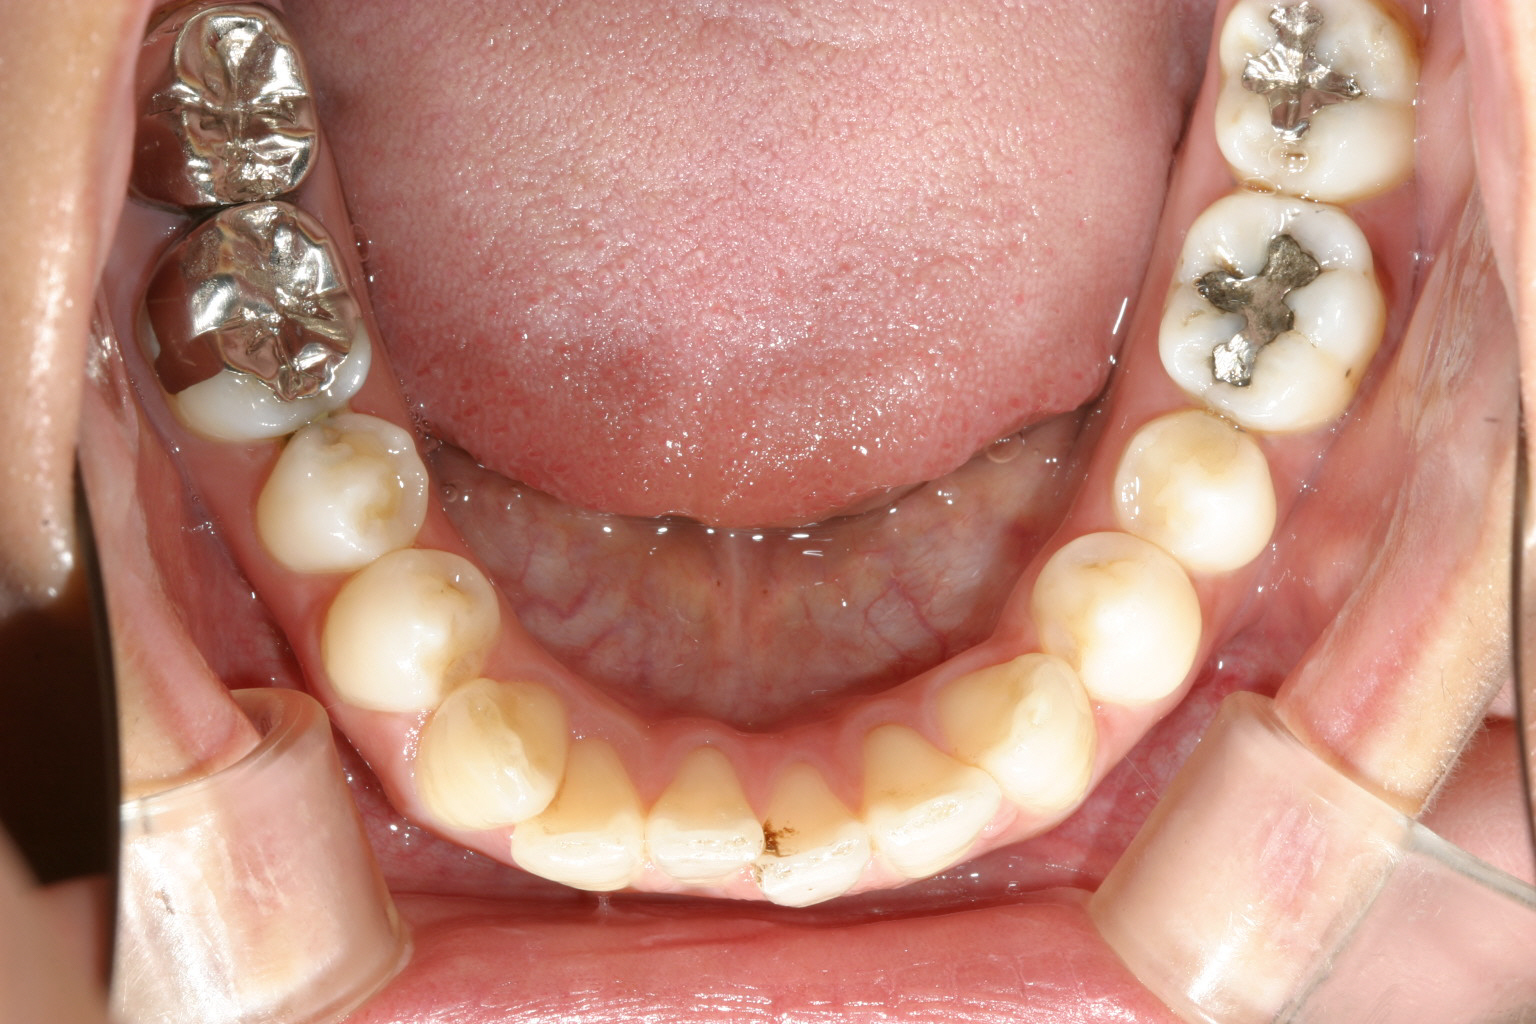

下顎は少しの叢生が有ります。

下顎も綺麗に改善されています。